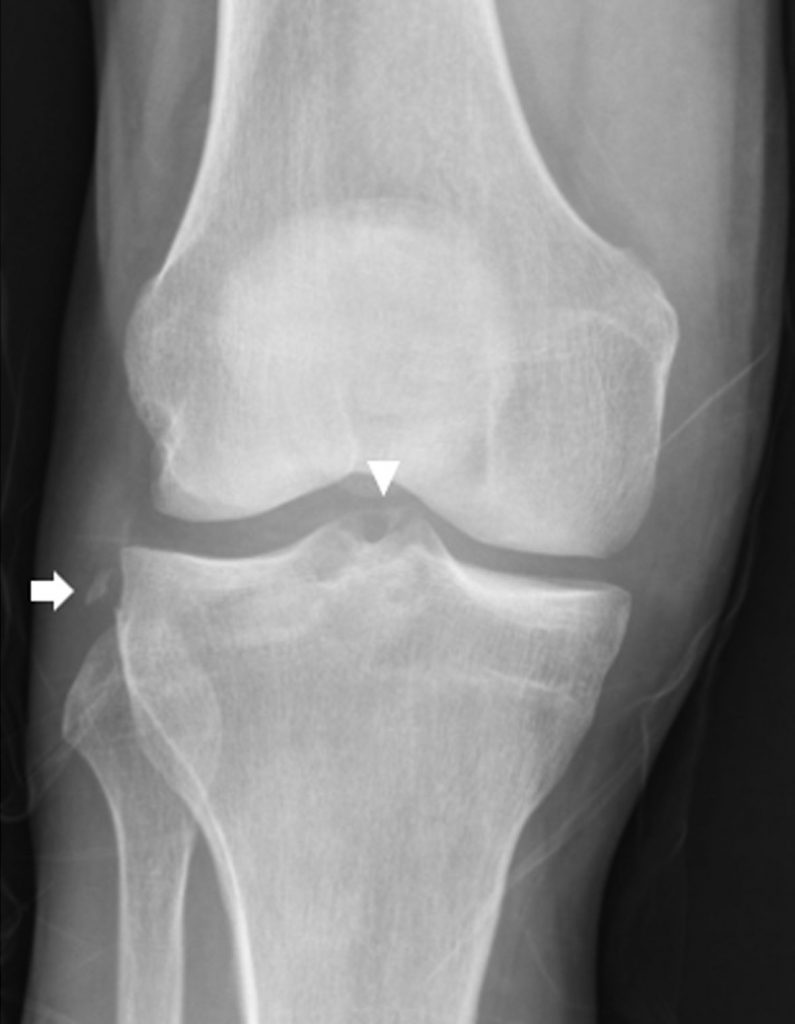

Certaines fractures sont évocatrices de lésions ligamentaires, comme la fracture-arrachement de la partie latérale du plateau tibial (fracture de Segond) presque toujours associée à une rupture du LCA, ou la fracture-arrachement du massif spinal qui est un équivalent de rupture du LCA chez l’adulte jeune. (figure 79.1).

Fig. 79.1 Radiographie du genou de face montrant une fracture-arrachement de la partie latérale du plateau tibial, ou fracture de Segond (flèche), associée à une fracture-arrachement du massif spinal (tête de flèche)

Source : CERF, CNEBMN, 2022.